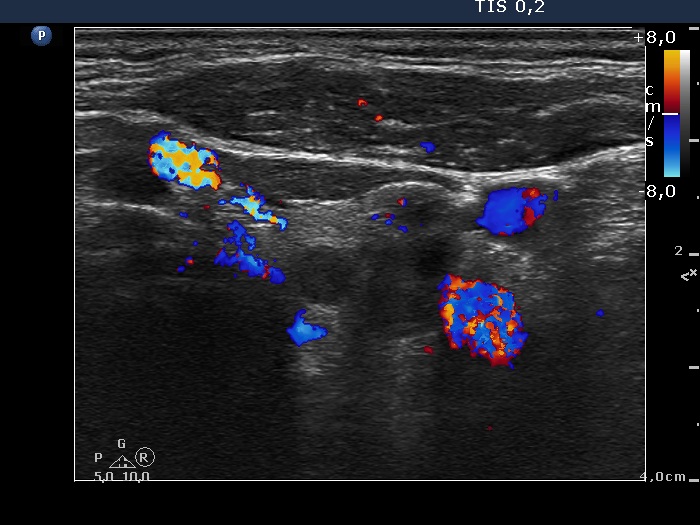

Ultrasonography. The right thyroid was composed of multiple discrete lesions with different echogenicities. The lobe was extremely enlarged with the dimension of 55x65 xminimum 120 mm (width, depth, and length, respectively) and spread retotracheal and substernal. The lower pole of the lobe could not be visualized while swallowing. The left thyroid was normal-sized and contained several hypoechogenic lesions. There was a moderately hypoechogenic nodule in the right lobe. The lesion presented neither halo nor perinodular blood flow.